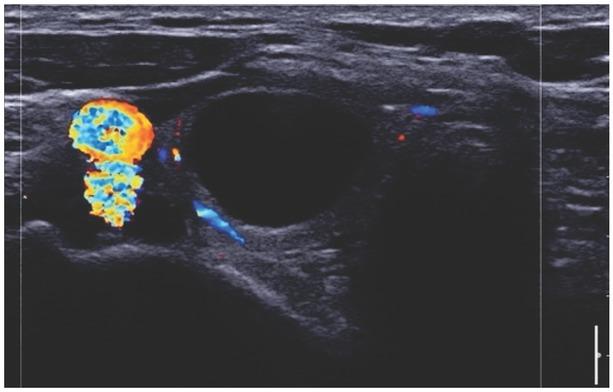

Fig. 6